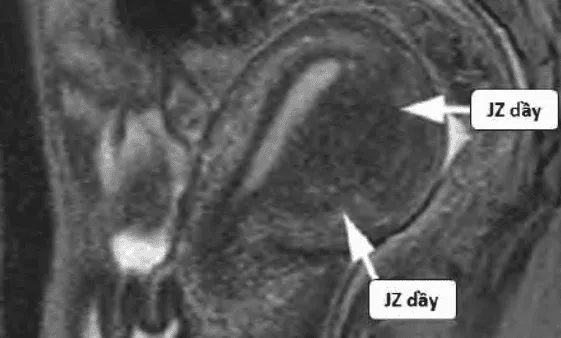

Hình ảnh “Cộng hưởng từ của adenomyosis”.

Thuyết tử cung hai nguồn gốc: Tử cung phát triển từ hai nguồn Muller và trung mô, gặp nhau tại vùng kết nối (JZ). Adenomyosis xuất phát từ chồng lấn bất thường tại JZ.

Hình ảnh “Tử cung bình thường trên MRI”.

Hình ảnh “Adenomyosis trên MRI”.